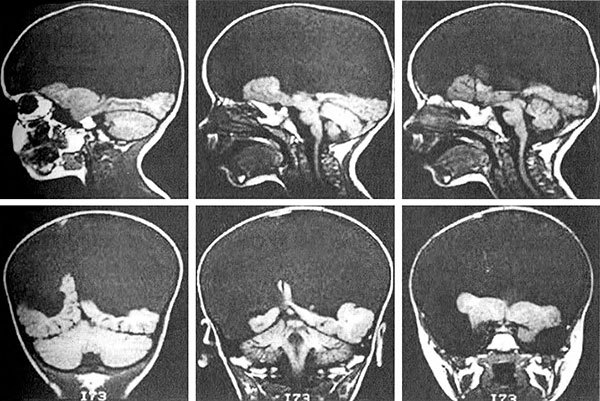

Рис. 9.1. Магнитно-резонансные томограммы головы ребенка, страдающего гидроанэнцефалией. Большие полушария почти полностью отсутствуют, и вместо них череп заполнен спинномозговой жидкостью.

Одним из ярких свидетельств того, что сознание распространено гораздо шире, чем мы склонны признавать, может служить жизнеспособность и явная сознательность редких детей, рождающихся без коры больших полушарий головного мозга. Происходящий во время зародышевого развития микроинсульт или другая подобная аномалия может приводить к разрушению значительной части обоих больших полушарий. Неудивительно, что в результате дети появляются на свет с серьезными расстройствами, такими как плохое зрение или неспособность обучаться языку. Но при этом, как показал шведский нейробиолог Бьорн Меркер, некоторые из таких детей (несмотря на отсутствие у них почти всех отделов мозга, которые мы обычно связываем с сознанием) демонстрируют настоящее эмоциональное поведение, смеются и плачут, когда это уместно, и реагируют на окружающее вполне по-человечески. Я уже упоминал, что многие эмоциональные центры расположены у нас в древних отделах мозга, таких как мозговой ствол и средний мозг, похожие почти у всех позвоночных. С помощью магнитно-резонансной томографии Дерек Дентон показал, что именно эти древние структуры отвечают за такие базовые эмоции, как жажда или боязнь задохнуться. Вполне возможно, что корни сознания нужно искать вовсе не в «новомодной» коре больших полушарий (они, разумеется, вносят огромный вклад в сознание, однако лишь разрабатывают его на уже имеющейся основе), а в плотно структурированных древних отделах мозга, свойственных не только нам, но и широкому кругу других животных. А если так, то переход от нервных импульсов к чувствам неизбежно теряет часть окружающей его мистической ауры.